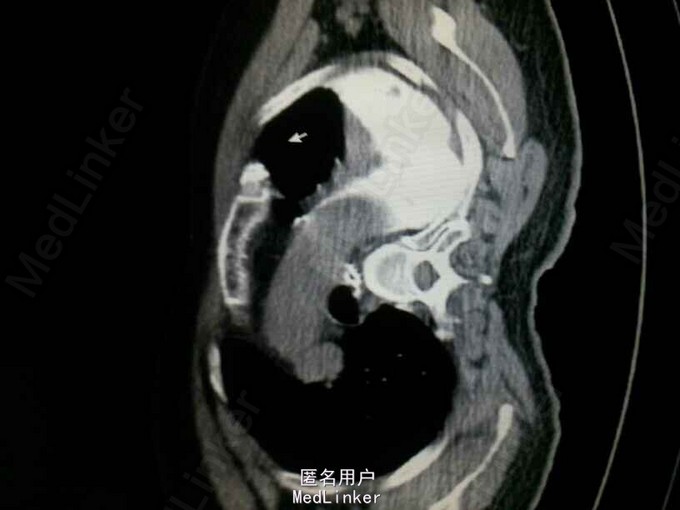

查体:气管居中,左肺呼吸音弱,右肺呼吸音尚可。未闻及湿啰音。胸腔引流管可见褐色浑浊液体引出。 腹部CT肝脾胰未见异常,胆总管扩张。 食管造影:食管下端撕裂,食管胸膜瘘。 胸CT左肺气胸,左侧胸腔内高密度影,考虑造影剂漏入胸腔。左肺实变,右侧少量胸腔积液。

诊断:自发性食管破裂。 治疗:急诊行胸腔闭式引流。后行左剖胸食管破裂修补。术中见胸腔污染严重,见菜叶,消化液等。后纵膈可见较多脓性分泌物,食物残渣,坏死组织。食管裂口处上方可见5cm纵向肌层及粘膜层撕裂口,相应位置处可见纵膈胸膜撕裂口。术后予肠内肠外营养,舒普深,泰能,稳可信,抗感染,术后反复行2次食管造影,仍存在食管破裂口,术后一月行胃镜及食管支架植入术。第二天行进食流质及半流质通畅,平稳出院。